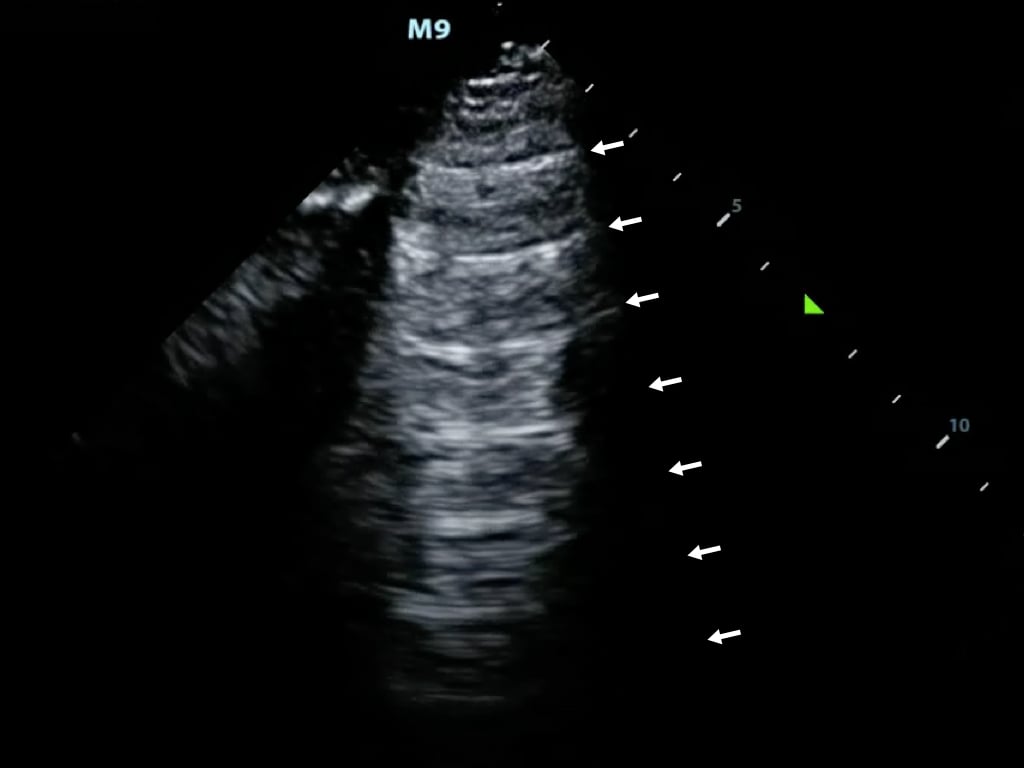

- Reverberation occurs when sound encounters two highly reflective layers

- The sound is bounced back and forth between the two layers before returning to the transducer

- The probe detects prolonged travel time and correlates with a further distance, displaying additional ‘reverberated’ images in a deeper tissue layer (Figure 9)

- Figure 9. Reverberation artifact from the pleural line